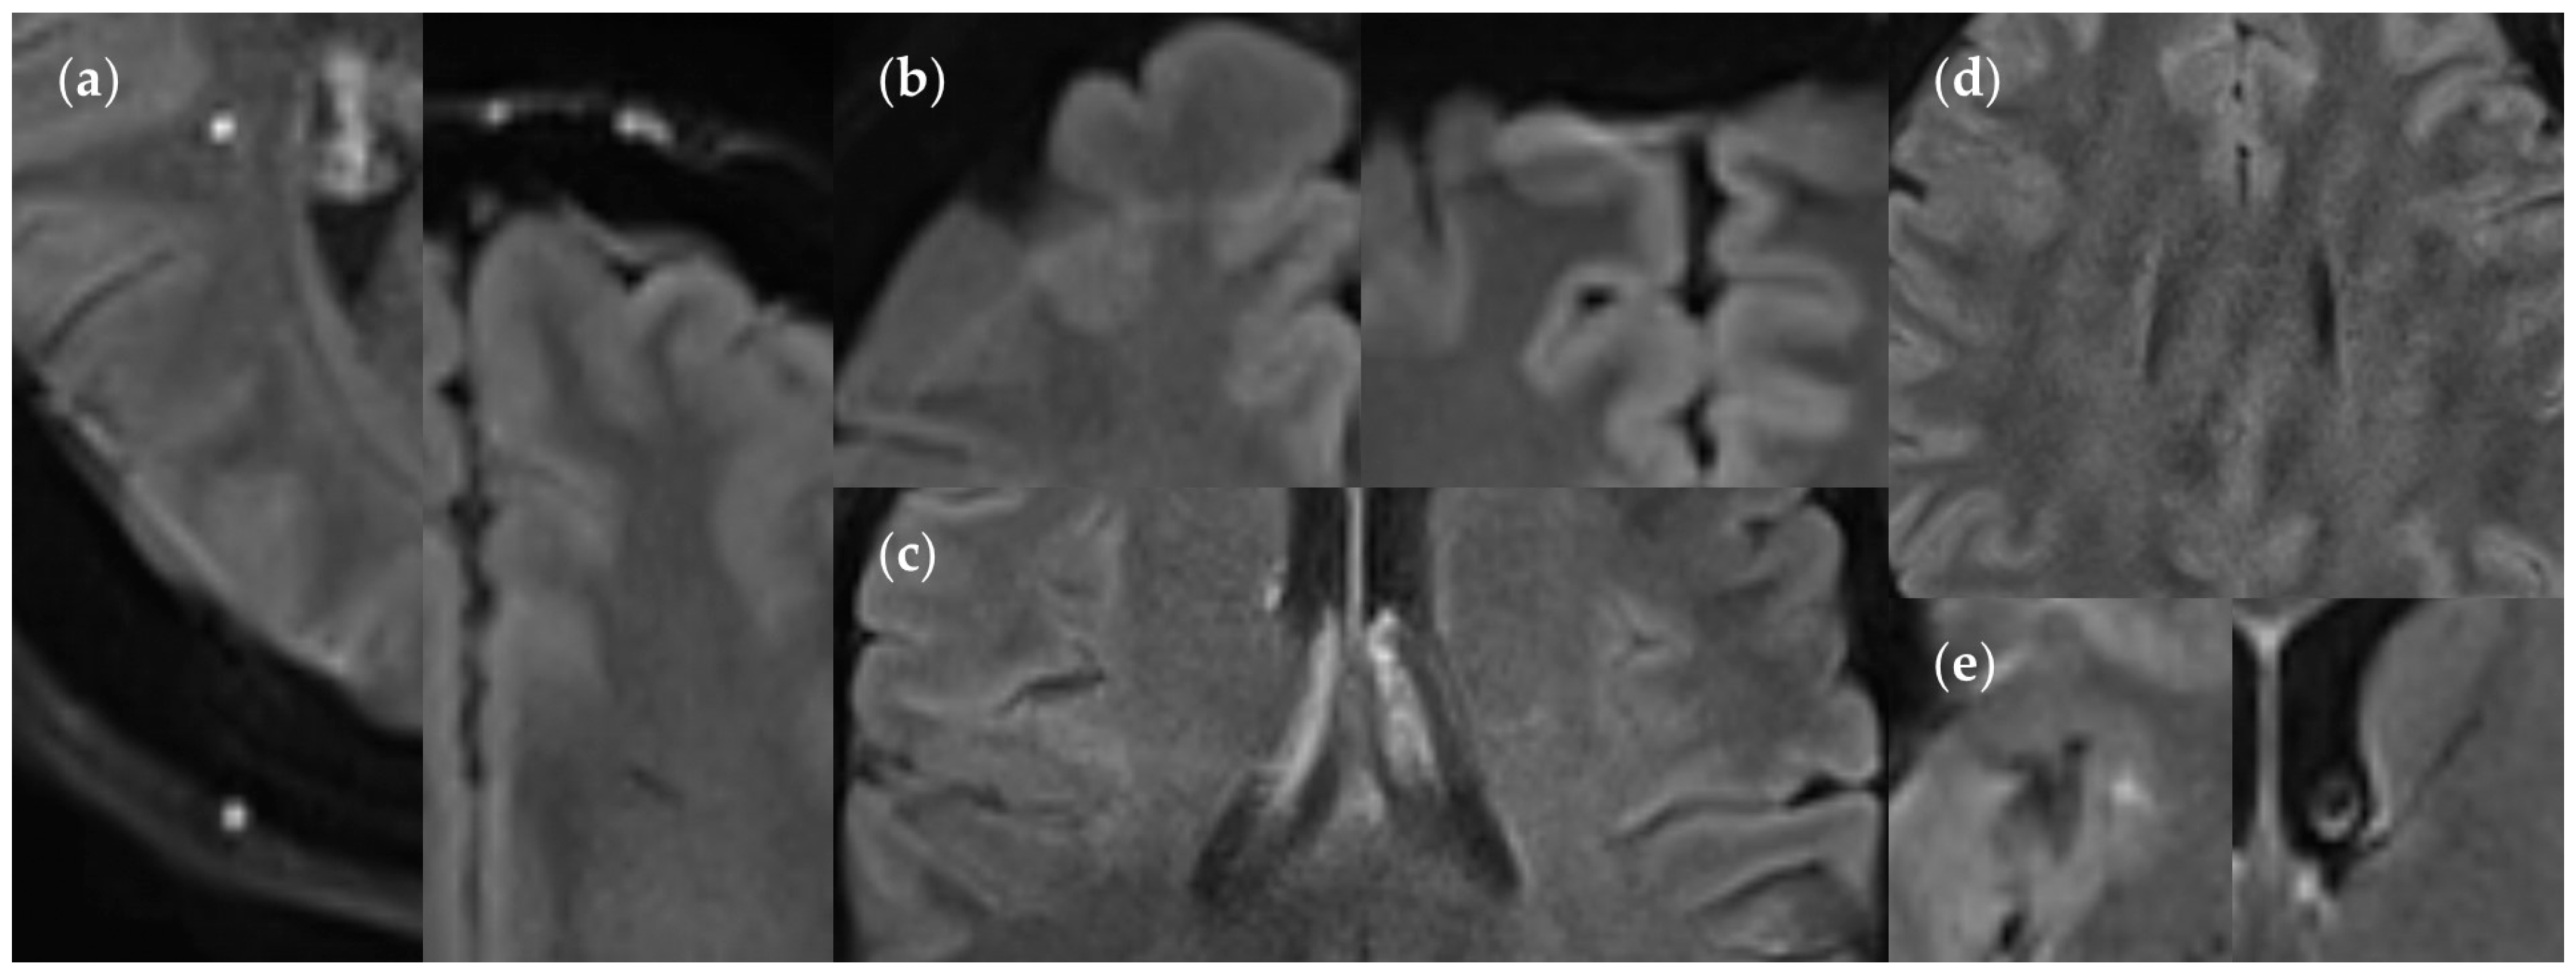

3.2.3. Dependence on Size and Location within FLAIRUF

3.3.3. Positional Dependence of SNR and CNR in FLAIRUF

4.3. Limitations of the FLAIRUF Images

4.4. Considerations on Ratings for Lesion Conspicuity in FLAIRUF

4.5. Outcomes Correlated with Technical Features